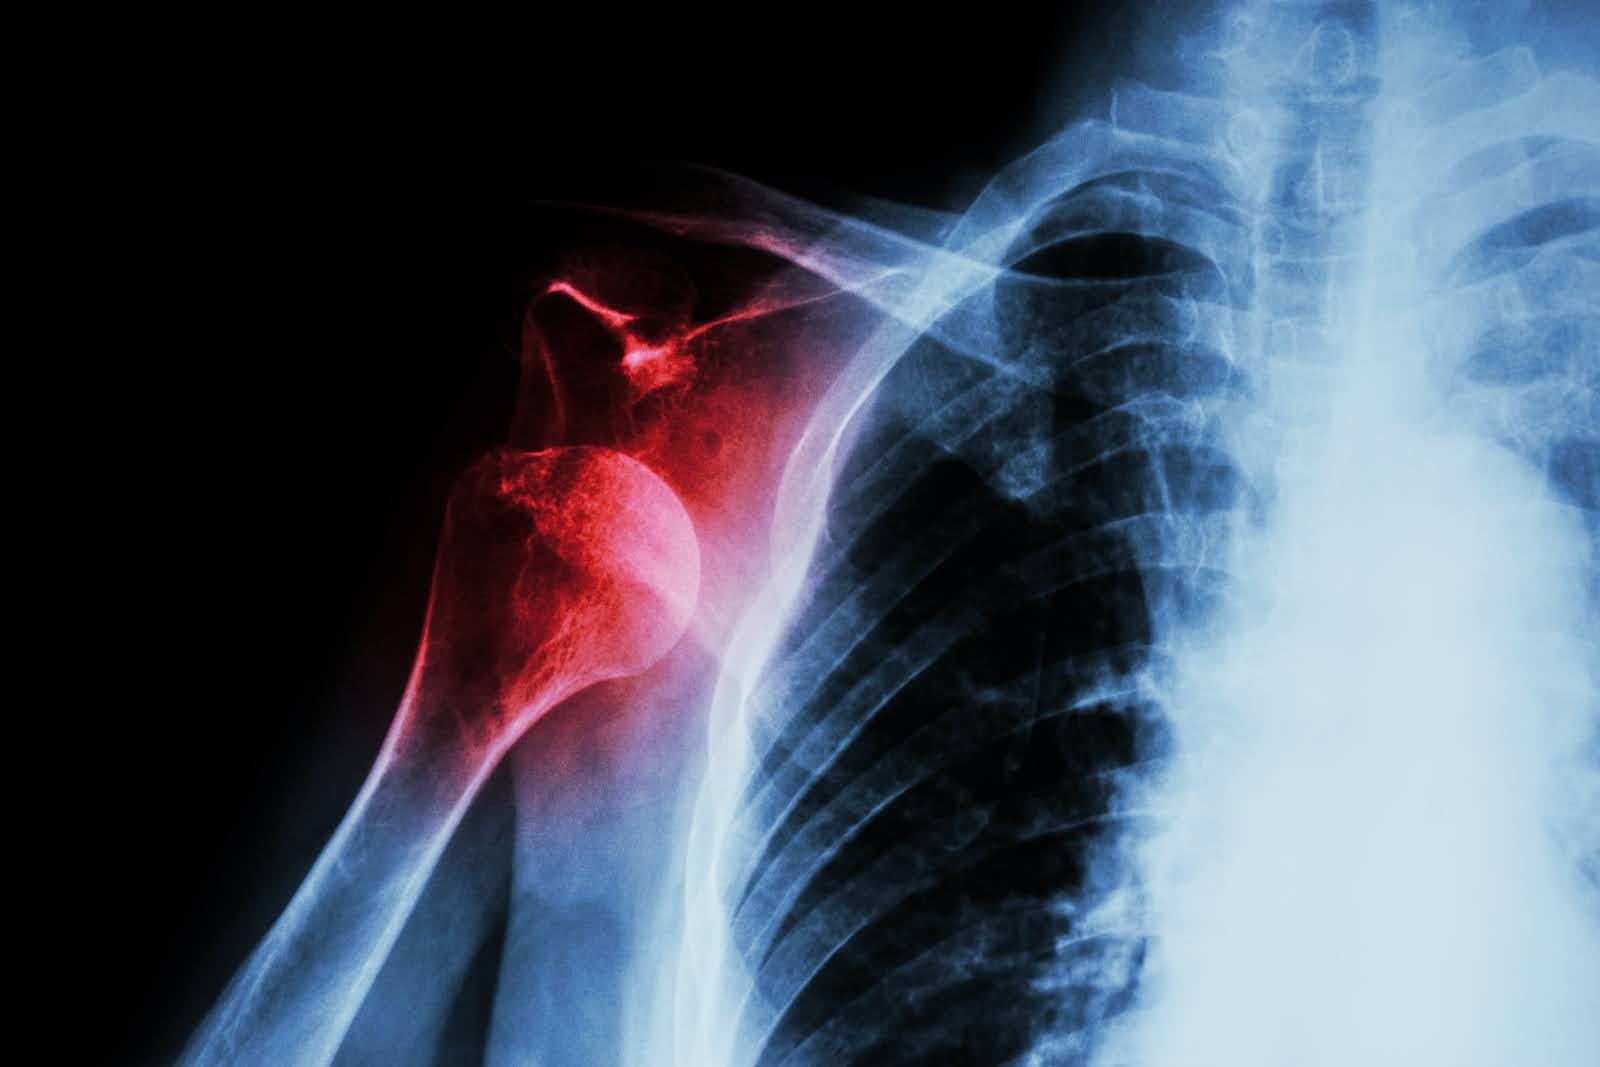

Shoulder dislocations represent one of the most common orthopedic emergencies, yet the direction of dislocation significantly impacts diagnosis, treatment, and outcomes. While both anterior and posterior dislocations involve the separation of the humeral head from the glenoid socket, they present with vastly different clinical pictures that can challenge even experienced healthcare providers.

The shoulder joint's unique structure makes it the most mobile yet unstable joint in the human body. When examining anterior vs posterior shoulder dislocation, the fundamental difference lies in the direction the humeral head (upper arm bone) moves out of the glenoid socket (shoulder socket).

Proper radiographic evaluation requires multiple views to accurately identify the direction of dislocation and rule out associated fractures.

Posterior dislocations are missed in up to 79% of initial evaluations, primarily due to their subtle presentation onanteroposterior X-rays. Healthcare providers must maintain high clinical suspicion and obtain appropriate imaging views to avoid this diagnostic pitfall.